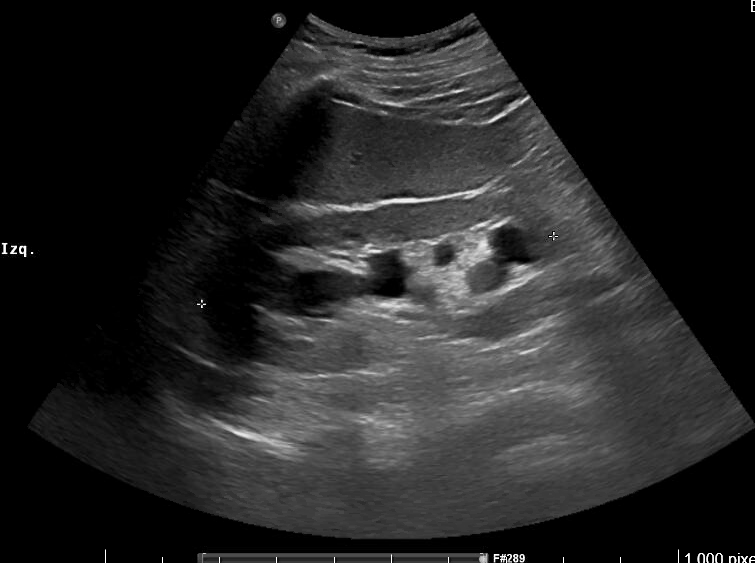

Imagen 1. Riñón derecho: hidronefrosis grado II. Tamaño 11.2 cm.

Imágenes 2 y 3. Riñón izquierdo: hidronefrosis grado II. Disminución del grosor cortical. Tamaño 11.5 cm.